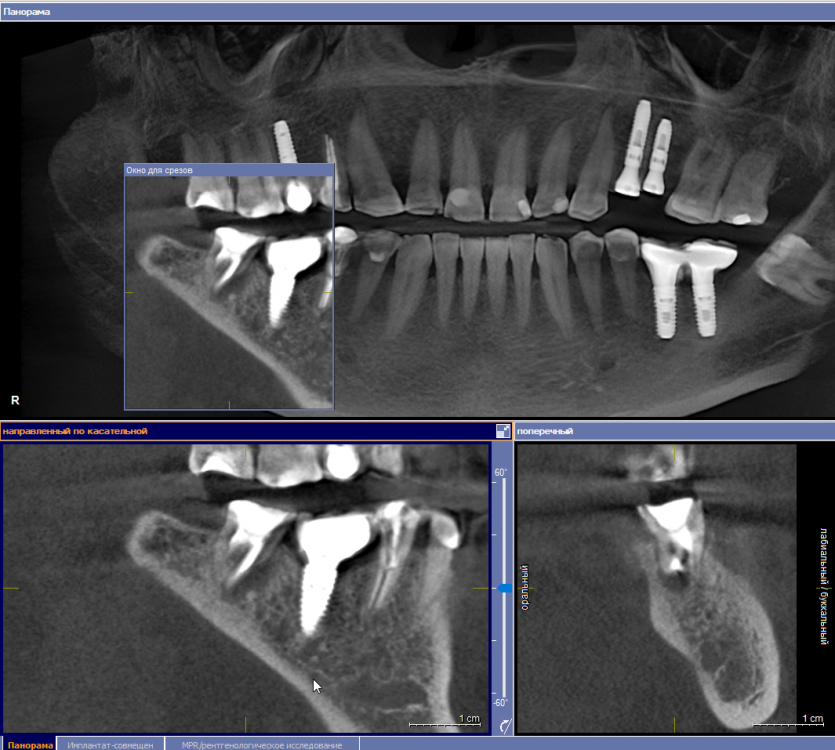

se77777 Опубликовано 19 сентября, 2022 Поделиться Опубликовано 19 сентября, 2022 Добрый день, 37. Эндодонтическое лечение с микроскопом 2,5 года назад. Слабая невнятная боль возвращалась от случая к случаю. Даже была тенденция к затягиванию полости. Но, похоже, не получилось. После коронавируса и серьезной нагрузки, впервые боль на короткое время обострилась. Полость, похоже, растет. От дна полости кисты до канала нерва 6 с небольшим мм. Показано ли в таком случае одномоментное удаление и имплантация? Спасибо. Ссылка на комментарий

red_butler Опубликовано 19 сентября, 2022 Поделиться Опубликовано 19 сентября, 2022 3 часа назад, se77777 сказал: Показано ли в таком случае одномоментное удаление и имплантация? Срезы не совсем корректные, но одномоментная имплантация скорее всего возможна 1 1 Ссылка на комментарий